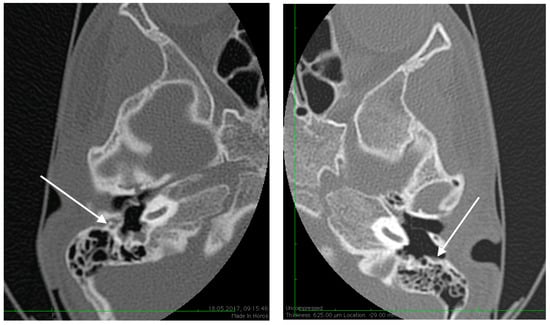

No family history of hearing problems could be elicited. A high resolution CT scan revealed bilateral middle ear anomalies. There were no images of the oval window and stapes suprastructure in his left ear, with abnormal facial nerve canal position and patent foramen spinosum (Figure 2 and Figure 3). The stapes suprastructure and the oval window were also missing to the contralateral (right) ear with a wide facial nerve canal between the geniculate and the round window niche and an abnormal traject on its mastoid segment. No foramen spinosum was observable on the right side (Figure 4, Figure 5 and Figure 6). Furthermore, surgery was carefully planned to investigate the middle ear.

Figure 2.

High resolution axial CT scan of left temporal bone showing a missing oval window and stapes suprastructure (arrow) on both sides.

Figure 3.

High resolution axial CT scan of left temporal bone exposing the patent foramen spinosum (arrow).

Figure 4.

High resolution axial CT scan of right temporal bone exposing the unusual wide facial canal and the missing oval window on the right side (arrow).

Figure 5.

High resolution axial CT scan of right temporal bone exposing the missing foramen spinosum (arrow).

Preoperative CT imaging of middle ear surgery patients is mandatory and careful interpretation of the results can sometimes prevent accidental injuries brought to a PSA. The usual findings are a small, abnormal, canaliculus leaving the carotid canal or the facial nerve, a straight line structure crossing over the promontory, an unusual widening of the fallopian canal or a different canal parallel to it between the geniculate and the oval window niche and absence of the foramen spinosum []. Our CT findings coincide with some of the aforementioned signs, as there can be seen no trace of the foramen spinosum in the affected ear (Figure 5), in contrast to the contralateral ear (Figure 3). There is also a widening of the facial nerve canal that can be observed in Figure 4. It came as no surprise that the stapes could not be described in the CT images, as the literature review acknowledges the possible stapes malformations that come along with PSA.